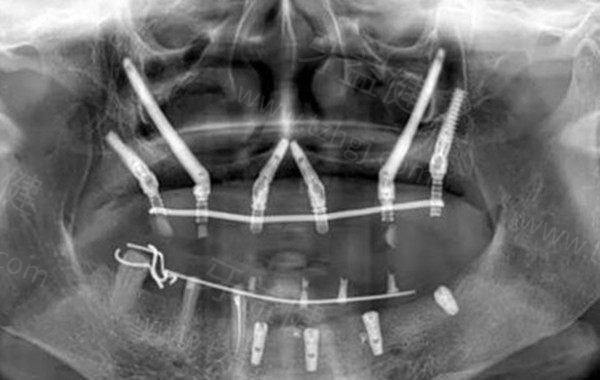

鼎植口腔拥有的 VIIV穿颧穿翼种植技术(简称VIIV技术)是业内公认的重大突破,该技术主要针对传统种植技术无法解决的骨量不足问题。

这种技术的创新性在于它打破了传统种植牙对牙槽骨条件的限制,通过颧骨与翼板等更稳固的骨骼结构来固定种植体,实现了所谓的"无土栽培"式种植。

VIIV技术的临床优势表现在多个维度:首先,它避免了传统种植需要先 进行植骨手术的复杂过程,将原本需要6-12个月的治疗周期缩短至1天内完成,实现了"当天种牙、当天戴牙"的即刻负重成果。其次,该技术采用微创切口(创口小于5mm),相比传统植骨手术20-30mm的创口。

除了VIIV技术外,鼎植口腔还熟练掌握All-on-4、All-on-6半口/全口即刻种植、数字化导板种植等数字化技术。医院引进了智慧种牙机器人等数字化设备,将医生经验与机器人的执行结合,使种植体定位精度误差仅0.1毫米,大大提高了手术的成功概率和准度。这些技术的综合应用,使鼎植口腔在处理各类疑难种植病例方面表现出色,包括上颌窦位置低、牙槽嵴重度吸收、颌骨缺损等传统种植手段难以解决的情况。